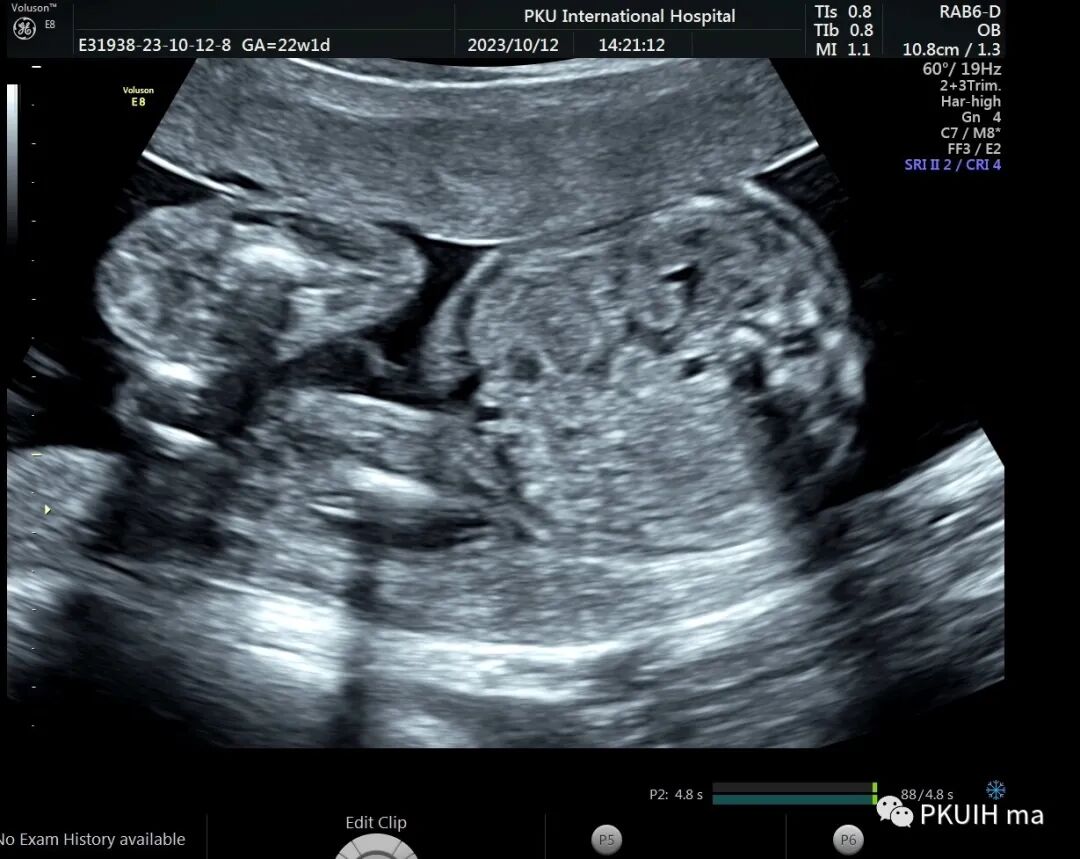

今天看到一22周的胎儿,一侧肾区未见肾脏结构,肾上腺呈平卧征,肾动脉也未显示,在盆腔见到一个发育不良的肾脏回声。

右肾大小位置正常,右肾动脉可见,左肾动脉缺如,正常的左肾区未见肾组织回声,可见肾上腺平卧。于膀胱后上方见一肾组织回声,大小约1.5x1.4x1.0cm,皮髓质分界欠清晰,血供来源于髂动脉。